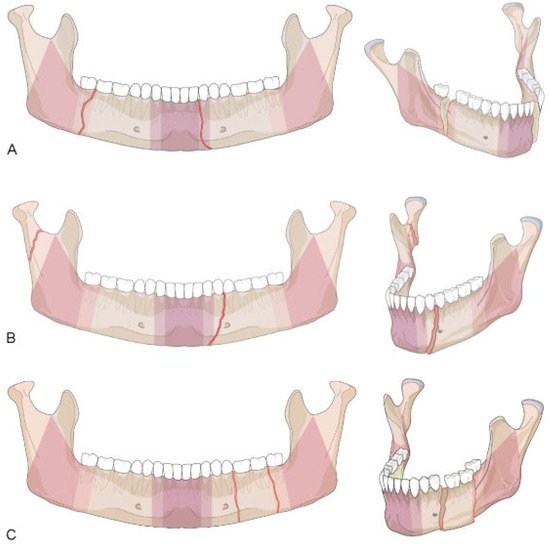

Mandibular Body Region

Confinement—Fractures Located within Anatomical Regions

- • “Confined” fracture pattern: the fracture, irrespective of its morphology, remains within an anatomical region (including a transition zone) and does not extend into an adjoining region across a transition zone.

- • “Nonconfined” fracture pattern: the fracture crosses at least one transition zone and may extend over one or more adjoining region.